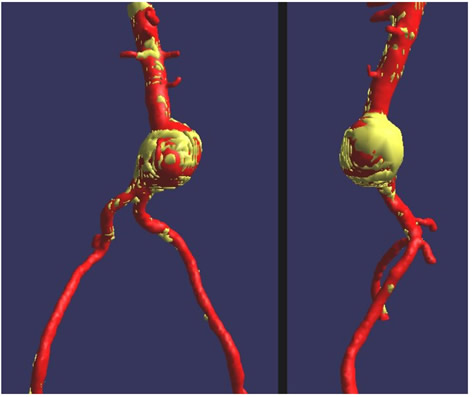

- The main trunk is flushed with heparinized solution, advanced into the proximal neck, positioned just inferior to the lowest renal artery, and oriented so that the contralateral limb gate can be easily accessed. The orientation of the contralateral gate is performed using the manufacturer’s radiopaque markers at the crown of the trunk and/or the stent graft bifurcation under fluoroscopic guidance. A repeat angiogram is commonly performed to reconfirm the positioning of the device within the aorta. Subsequently, the main trunk is deployed (Figures 2, 3), opening the contralateral limb gate.